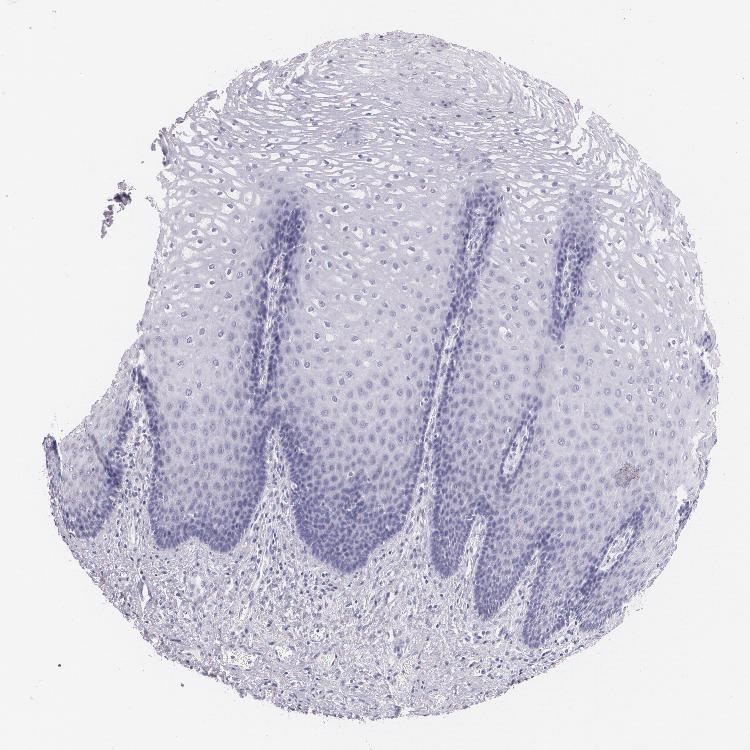

ESOPHAGUS - Antibody stainingi

Antibody staining in the annotated cell types in the current human tissue is reported as not detected, low, medium, or high, based on conventional immunohistochemistry profiling in selected tissues. This score is based on the combination of the staining intensity and fraction of stained cells.

Each image is clickable and will lead to virtual microscopy that enables deeper exploration of all samples and also displays staining intensity scores, fraction scores and subcellular localization as well as patient and tissue information for each sample.

Antibody HPA010122Antibody HPA071006Antibody CAB001999Antibody CAB002000

Squamous epithelial cells MediumNot detectedNot detectedLow